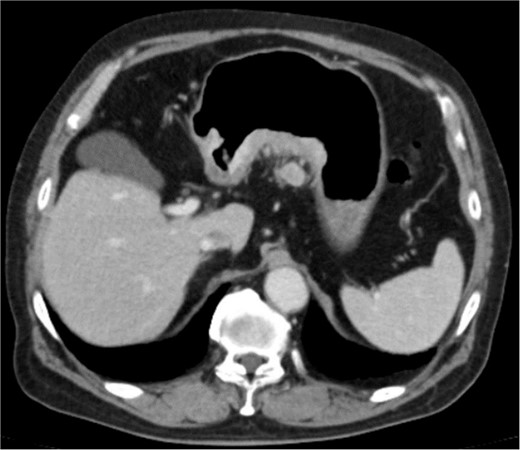

An 83-year-old man visited due to discomfort in the stomach. The patient underwent upper endoscopy that revealed a large tumor in the stomach (Fig. 1). The histological diagnosis was moderately differentiated tubular adenocarcinoma. Computed tomography (CT) revealed thickening of the gastric wall and bulky lymph nodes around the pancreas (Fig. 2). The patient underwent subtotal gastrectomy with Roux-en-Y reconstruction. The metastatic lymph nodes around the pancreas were removed. Abdominal drainage from Winslow’s foramen was performed. The pathological result was pT4aN3aM0 and Stage IIIB [1].

Clinical findings of contrast-enhanced CT. CT revealed the thickness of gastric wall and enlarged lymph nodes of lesser curvature side.